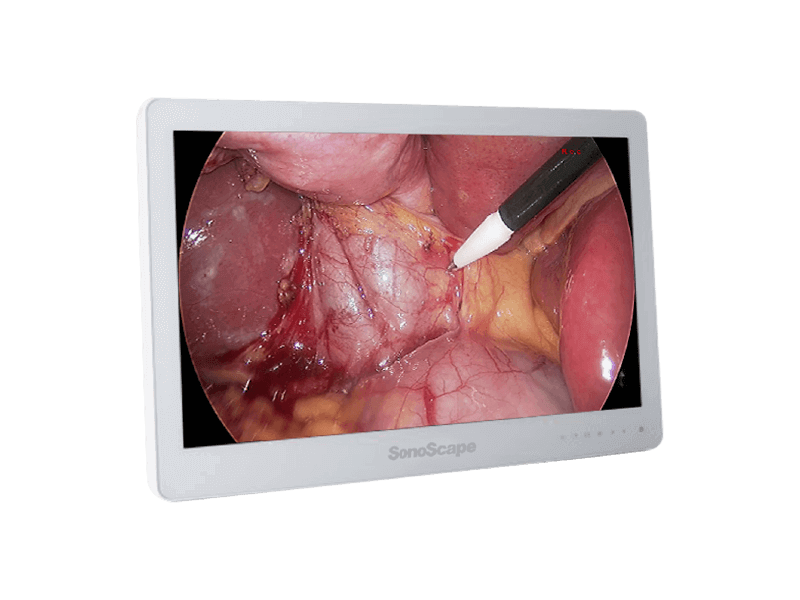

SV-M2K30

全高清内窥镜摄像系统

全高清内窥镜摄像系统

采用3片CMOS图像传感器,输出1920*1080P、60FPS全高清数字信号,提供稳定的腔镜视野,给予术者极佳的视觉体验,让手术更轻松,更精细!

1080P视频输出